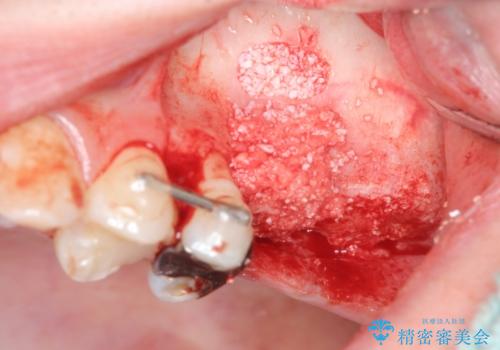

奥歯を2本失ったのち、しっかりと噛める環境へと整備するため、しっかりと骨の造成を行い清掃性を高めたインプラント治療を行っていくこととしました。

インプラントの仕上がりを見越して、ただ埋入するだけではなく長期的な予後を見込むには清掃のしやすい環境を整備することが大切です。

今回は大きく吸収してしまった歯槽骨をしっかりと造成することで、歯間ブラシを行いやすいインプラント周囲環境を整備することができました。